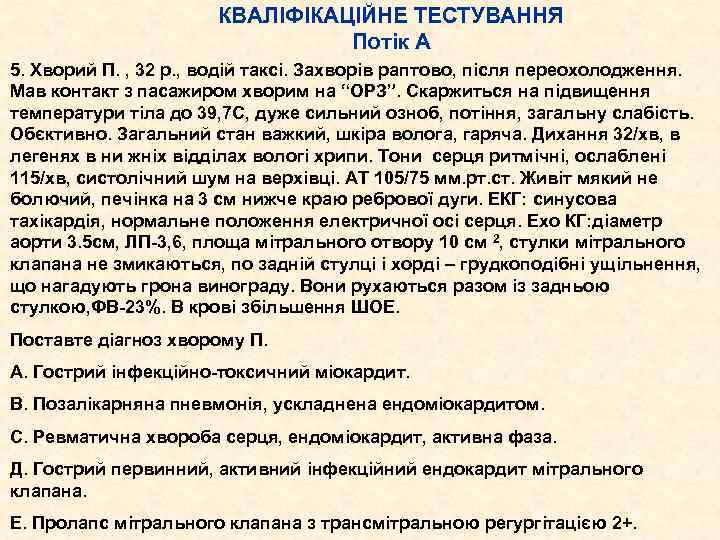

КВАЛІФІКАЦІЙНЕ ТЕСТУВАННЯ Потік А 5. Хворий П. , 32 р. , водій таксі. Захворів раптово, після переохолодження. Мав контакт з пасажиром хворим на “ОРЗ”. Скаржиться на підвищення температури тіла до 39, 7 С, дуже сильний озноб, потіння, загальну слабість. Обєктивно. Загальний стан важкий, шкіра волога, гаряча. Дихання 32/хв, в легенях в ни жніх відділах вологі хрипи. Тони серця ритмічні, ослаблені 115/хв, систолічний шум на верхівці. АТ 105/75 мм. рт. ст. Живіт мякий не болючий, печінка на 3 см нижче краю ребрової дуги. ЕКГ: синусова тахікардія, нормальне положення електричної осі серця. Ехо КГ: діаметр аорти 3. 5 см, ЛП-3, 6, площа мітрального отвору 10 см 2, стулки мітрального клапана не змикаються, по задній стулці і хорді – грудкоподібні ущільнення, що нагадують грона винограду. Вони рухаються разом із задньою стулкою, ФВ-23%. В крові збільшення ШОЕ. Поставте діагноз хворому П. А. Гострий інфекційно-токсичний міокардит. В. Позалікарняна пневмонія, ускладнена ендоміокардитом. С. Ревматична хвороба серця, ендоміокардит, активна фаза. Д. Гострий первинний, активний інфекційний ендокардит мітрального клапана. Е. Пролапс мітрального клапана з трансмітральною регургітацією 2+.